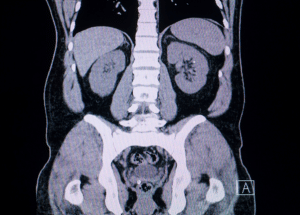

Computed tomography

Current management utilizes Computed tomography urography as the imaging modality of choice for the evaluation of the entire urinary tract and offers better detection and characterization of benign and malignant diseases. It allows for better visualisation of the lower urinary collecting system. CT scans are most useful in the evaluation of urologic tumors as it helps in localization, characterization and the stage of tumor. The indications for CT urography are quite like EU and are mainly used for assessment of the urinary collecting system in patients who present with hematuria.

Research have indicated that multidetector CT is more sensitive than EU in diagnosing Transitional cell carcinoma (TCC) of the upper urinary tract – its sensitivity being 95.8% as compared to 75%.

In the study of Abuhasanein and other authors evaluated the effectiveness of CT urography to exclude urinary bladder cancer and minimize the need for cystoscopy. This work revealed that CT urography in the corticomedullary phase yielded high accuracy in excluding bladder cancer. The negative predictive value was 99%, false negative rate 7% and false positive rate 1%.